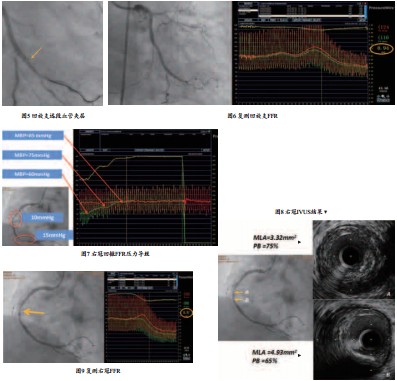

2、在一般的临床实践中,对于多支多处复杂病变常常会尽可能处理所有狭窄病变,该患者冠脉血管病变弥漫且严重,若单纯依靠冠脉造影结果,则可能盲目置入多枚支架,造成患者经济负担同时引起术后冠脉高闭塞率的发生。已有研究证实FFR在多支多处病变中的临床价值,PCI 术前行FFR对狭窄冠脉进行功能学评价,明确狭窄病变近远端血流压力情况,针对缺血病变进行支架置入,术后复测FFR数值,评价支架置入后血流压力效果,避免不必要支架的置入。同时,在本病例中,患者右冠近端及远端各置入一枚支架后,其中段冠脉造影提示60%~70%狭窄,为临界病变,遂行IVUS检查,结果提示为纤维斑块,斑块负荷76%,最小面积3.2mm2,且可观察到右冠近端新置入支架膨胀贴壁良好,复测右冠FFR为0.87,故未干预右冠中段临界病变。本病例患者通过IVUS联合FFR指导介入治疗,减少不必要的支架置入,降低再次血运重建发生率。